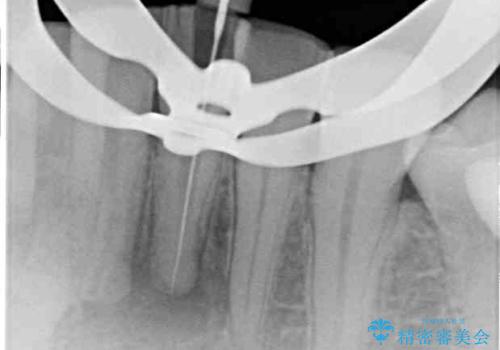

診査の結果、下顎左側中切歯の神経が失活していることが痛みの原因であり、根管治療を行う必要があると診断されました。

根管治療を行った後にオールセラミッククラウンにて補綴することとしました。

隣在歯にも根尖部の炎症が及んでいるように見えましたが、術前診査では神経が失活している様子がなかったため、まずは原因歯から処置を行うこととしました。

初回の根管治療後には痛みが速やかに改善し、6か月後のレントゲン写真では根尖の病変が消失していることが確認できました。